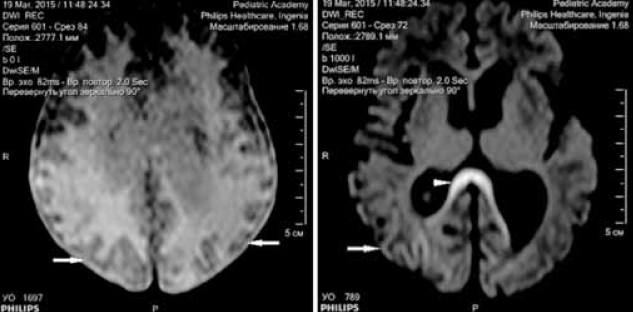

Выполнена магнитно-резонансная томография (МРТ) головного мозга через 3 недели после первого эпизода судорожных приступов (возраст ребенка на момент проведения исследования 6 недель) на аппарате Philips Ingenia1, 5 T. Получены Т1- Т2-взвешенные изображения, FLAIR-, DWI-изображения. На изображениях МРТ отмечаются зоны диффузных изменений МР-сигнала в теменно-затылочно-височных долях (рис. 6–8) без изменения архитектоники борозд и извилин. На представленных изображениях МРТ в аксиальной плоскости выявляются диффузные атрофические изменения коры головного мозга в затылочных долях, где толщина коры не превышает 1 мм, в сравнении с неизмененной корой в других отделах (рис. 6). На рис. 7 представлены изменения МР-сигнала (FLAIR) от измененной коры в теменно-затылочно-височных долях, без изменения архитектоники извилин. На DWI-картах сохраняются диффузные изменения МР-сигнала от структур затылочных долей, а также более отчетливо видны изменения сигнала от колена мозолистого тела (наконечник стрелки) (рис. 8).

Рис. 8. МРТ головного мозга ребенка в возрасте 6 недель с неонатальной гипогликемической энцефалопатией. Аксиальная плоскость, диффузно-взвешенные изображения (DWI). Стрелками указаны диффузные изменения МР-сигнала от коры головного мозга. Наконечник стрелки указывает на изменения колена мозолистого тела